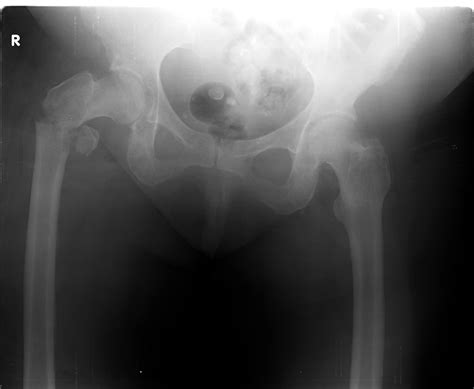

Bone fractures are a common injury that can occur due to various reasons such as accidents, falls, or sports injuries. An accurate diagnosis is crucial for effective treatment, and one of the most reliable methods for diagnosing bone fractures is through an X-ray of bone fracture. This non-invasive imaging technique provides detailed images of the bones, helping healthcare professionals to assess the extent of the damage and plan appropriate treatment.

An X-ray of bone fracture is a critical diagnostic tool that provides a clear view of the bone structure. This imaging technique uses electromagnetic radiation to produce images of the inside of the body. When it comes to diagnosing bone fractures, X-rays are particularly useful because:

X-rays work by passing a beam of electromagnetic radiation through the body. Different tissues absorb X-rays at different rates. Bones, being dense, absorb more X-rays than softer tissues like muscles and organs. This difference in absorption creates a contrast in the image, allowing healthcare professionals to see the bone structure clearly.

Interpreting X-ray Images

Interpreting X-ray images requires specialized training and expertise. Radiologists look for several key indicators when assessing an X-ray of bone fracture:

• Bone Alignment: They check if the bone fragments are properly aligned or if there is any displacement.

• Fracture Pattern: They identify the type of fracture (e.g., transverse, oblique, spiral) to understand the mechanism of injury.

• Bone Density: They assess the density of the bone to detect any signs of osteoporosis or other bone diseases.

• Soft Tissue Injuries: They look for any associated soft tissue injuries, such as swelling or muscle damage.

Radiologists use these findings to provide a detailed report to the treating physician, who then uses this information to develop a treatment plan.